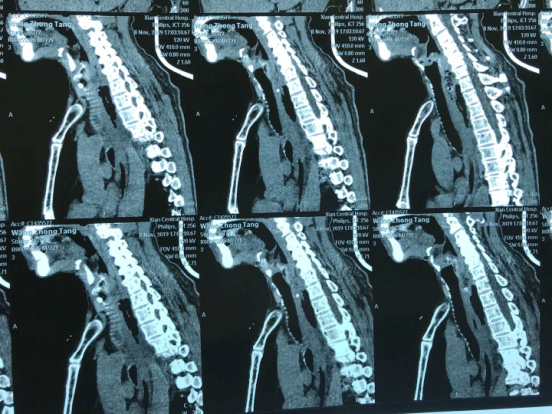

“大夫,快,我这人卡枣核5天没吃饭了,县医院说枣核又往下掉了”,2019118日下午,一位72岁老人在一群家属的搀扶下来到色花堂 耳鼻喉科门诊,门诊医师刘飞接诊患者询问病史,原来老人在村里“坐席”不慎将枣核误吞,在村卫生室、县城医院等多家医疗机构就诊,未能取出枣核,考虑枣核位置不断下移,建议转上级医院。至此患者因咽痛无法下咽已经5天滴水未进。患者既往糖尿病、冠心病,且未规范药物治疗,基础条件很差。考虑患者病情危重,予以迅速办理入院。权博源主任医师和尹黎波主治医师详细询问病史及查体后,为患者急查血:白细胞22,血糖、血酮、尿酮高,凝血象报危急值。患者食道异物食道穿孔合并严重感染,长期饥饿合并高血糖,手术风险很大。权博源主任医师亲自为患者制定治疗方案,立即抗感染、补液治疗,请内分泌科协助降糖降酮治疗,同时复查CT确定枣核现在位置,指标控制后立即手术。晚上10点,在麻醉科、手术室紧张有序的配合下,终于将枣核和覆盖在上方的鸡蛋样异物取出,术后患者平稳返回病房。